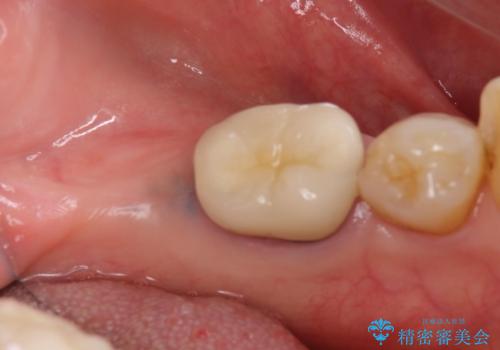

- 左下の大臼歯(6番)の根の治療を行いました。

左下6番の根管治療は六本木院の林院長にお願いしています。